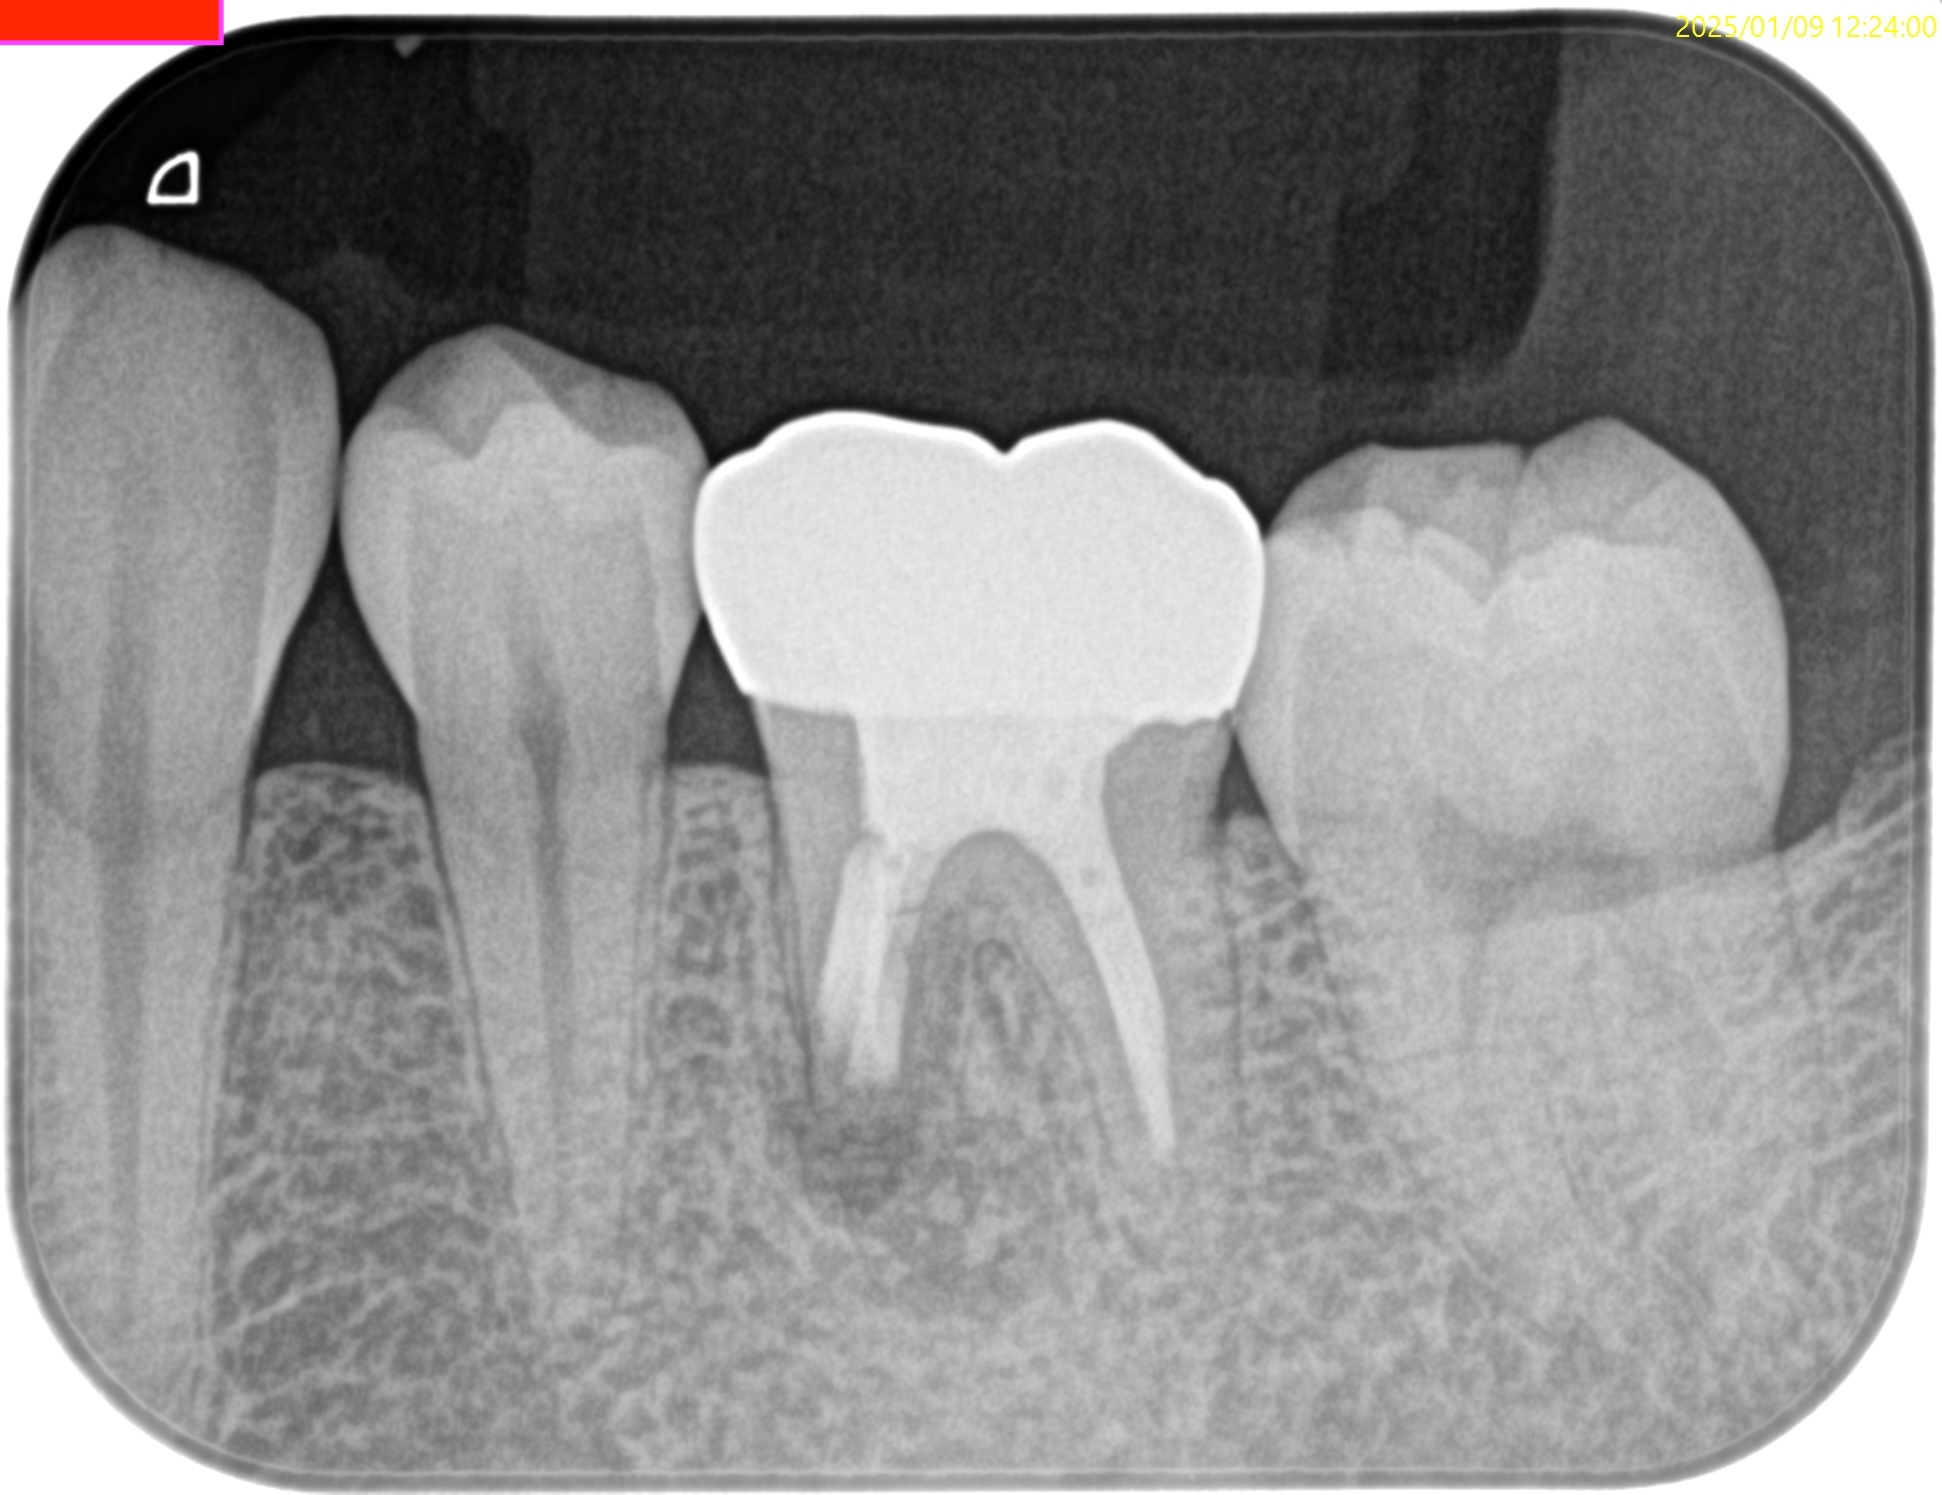

#19 M Apicoectomy(2025.1.9)

術後にPA, CBCTを撮影した。

問題はないだろう。